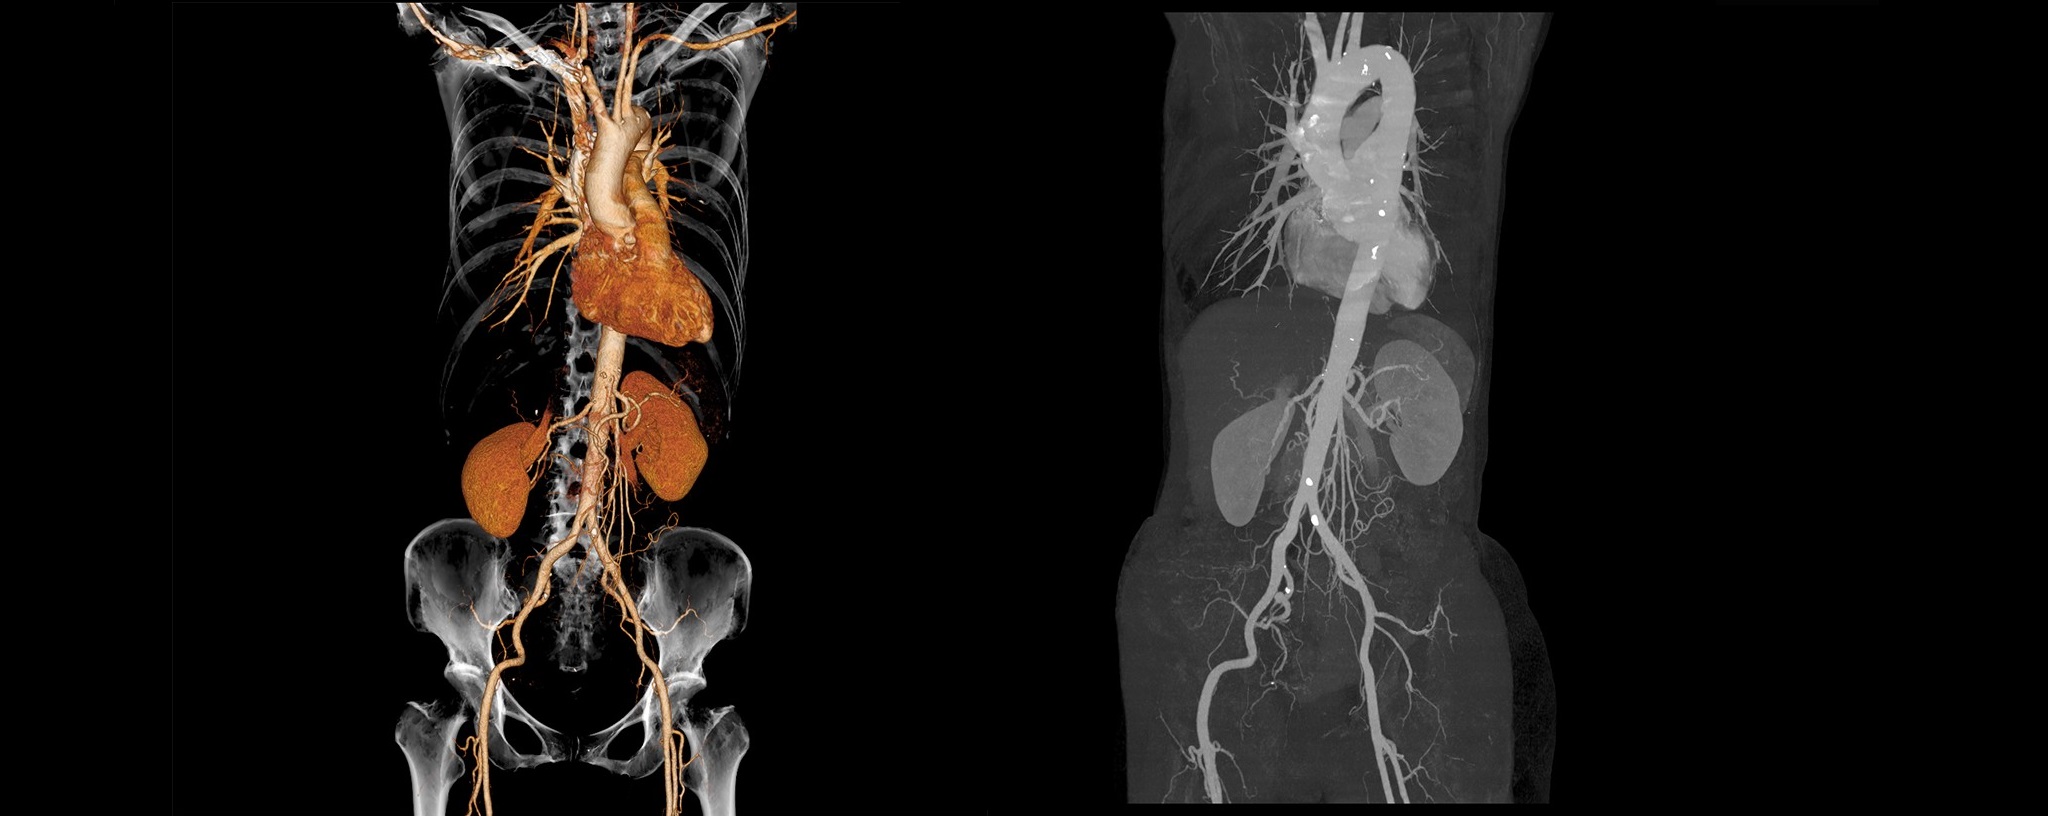

64列マルチスライスCT

最新のマルチスライスCTでより安全な精密検査が受けられます。

従来よりも検査時間が大幅に短縮されました。

2024年3月にCT装置を更新いたしました。

最新の深層学習などの新しいAI技術を採用した、64列128スライスCTスキャナ(富士 フイルムヘルスケア株式会社製「CT装置 Supria Optica」)を導入し、以前よりも短い時間で高画質の撮像が可能になりました。

この検査では、患者様が寝台に横になるだけで、苦痛なく頭部や胸部・腹部の断層像 (輪切り)が鮮明に撮れます。 とくに、らせん状に連続してデータを収集することができ(ヘリカルスキャン)従来の装置より広範囲の検査が行え、 脳出血・脳梗 塞・脳腫瘍・頭部外傷から胸部疾患および腹部臓器(肝・胆・膵・腎・膀胱・その他)疾患にいたるまで、 全身の診断が可能です。

CTアンギオグラフィ